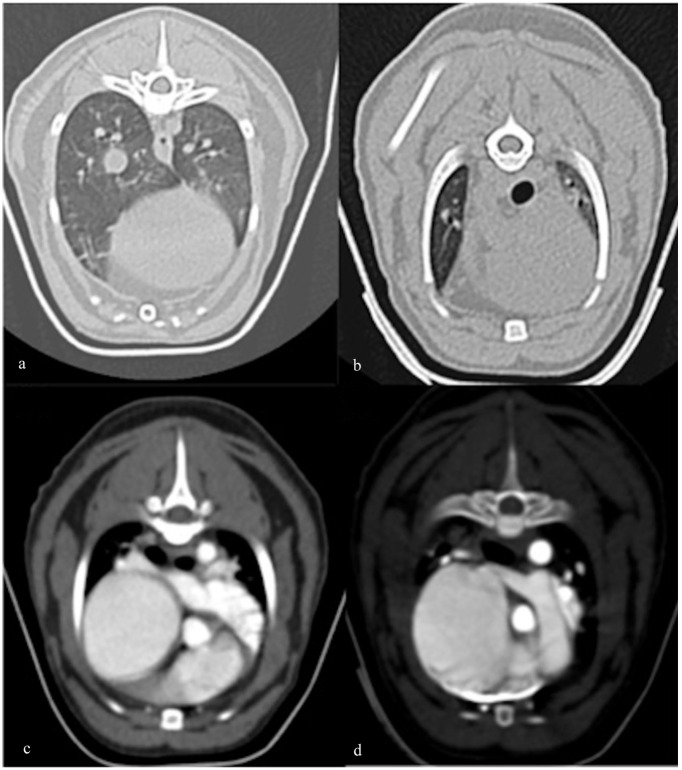

病例摘要:本报告描述了一只患有肺发育疾病和肺动脉高压高风险的幼猫的候选基因叉头盒 F1 (FOXF1) 的诊断结果、自然病史和遗传分析。一只 1 岁大的雄性全Chartreux猫因心脏杂音调查和运动不耐受而被转诊。超声心动图检查发现三尖瓣反流射流速度较快,并伴有右侧心脏变化,肺动脉高压的可能性很高。没有发现先天性心脏分流或左侧心脏病变,支持肺动脉高压的原发性心脏病因。对患者进行了广泛的实验室检查、胸部X光检查和CT检查。组织病理学鉴定(肺活检和随后的尸检)是最终诊断的必要条件。确诊八个月后,该猫出现右侧充血性心力衰竭,最终导致安乐死。从确诊到死亡的存活期为 12 个月:发育性肺病属于人类弥漫性肺病的一种,与肺动脉高压有关。描述猫肺发育障碍的兽医文献很少,本报告提供了有关临床表现和病情发展的信息以及全面的诊断工作,这可能有助于临床医生识别这种疾病。肺部活检是最终诊断的关键。未发现 FOXF1 的致病变异。

Case summary: This report describes the diagnostic findings, natural history and genetic analysis of the candidate gene Forkhead Box F1 (FOXF1) in a young cat with developmental lung disease and high probability of pulmonary hypertension. A 1-year-old male entire Chartreux cat was referred for cardiac murmur investigation and exercise intolerance. Echocardiography identified a high-velocity tricuspid regurgitant jet with right-sided cardiac changes, supporting a high probability of pulmonary hypertension. No congenital cardiac shunts or left-sided cardiac changes were found to support a primary cardiac cause of pulmonary hypertension. Extensive laboratory work, thoracic radiographs and CT were performed. Histopathological characterisation (lung biopsy and later post mortem) was necessary to reach the final diagnosis. Eight months after diagnosis, the cat developed right-sided congestive heart failure, eventually leading to euthanasia. Survival from diagnosis to death was 12 months.